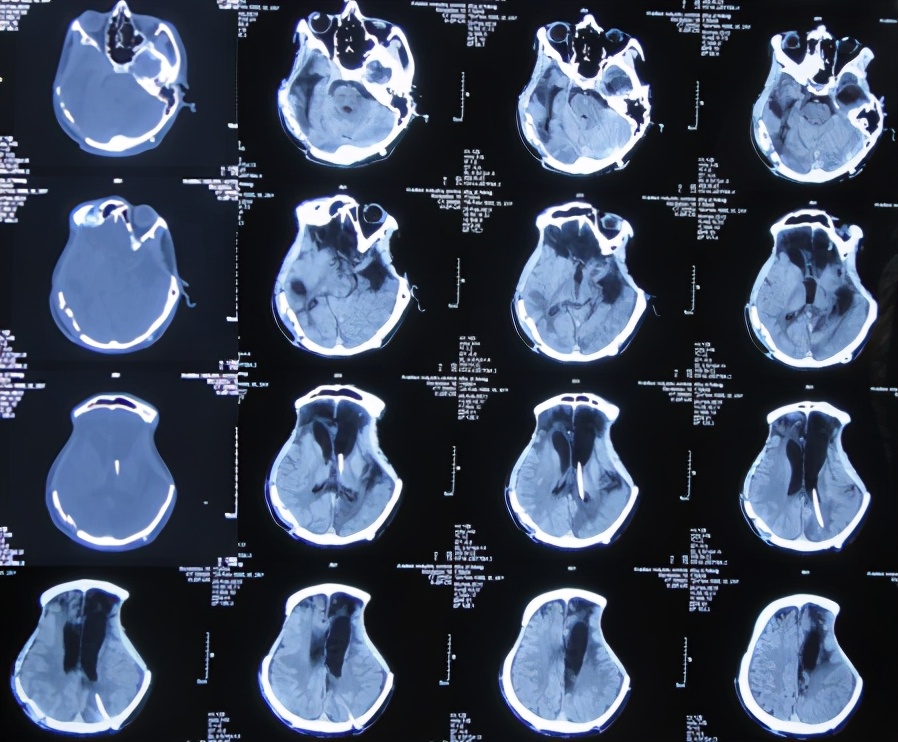

在第2家医院治疗45天时即2011年4月6日即开颅术后81天,仍能简单的遵嘱活动,能简单言语,如“爸爸、妈妈”;查头颅CT示:颅骨缺损,仍脑水肿,且出现脑室扩张( 图-4 );但没有给予处理。

图-4: 2011年4月6日头颅CT